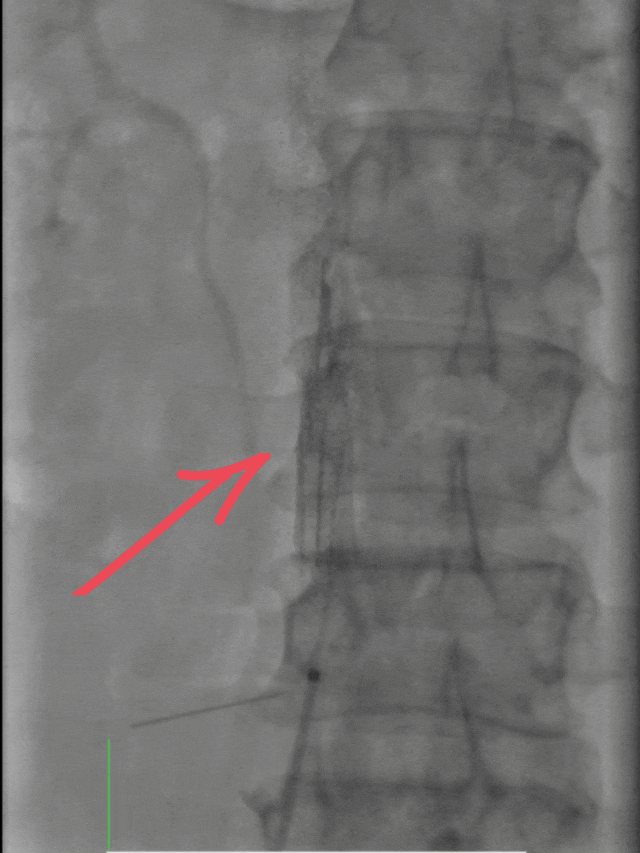

介入醫(yī)學(xué)團(tuán)隊緊急制定手術(shù)方案,一場與死神賽跑的介入治療隨即展開。手術(shù)分三步精準(zhǔn)推進(jìn):

首先通過下肢靜脈造影,清晰定位血栓位置與負(fù)荷;

隨后置入下腔靜脈濾器,如同在血管內(nèi)筑起“防護(hù)網(wǎng)”,有效預(yù)防血栓脫落引發(fā)更嚴(yán)重的肺栓塞;